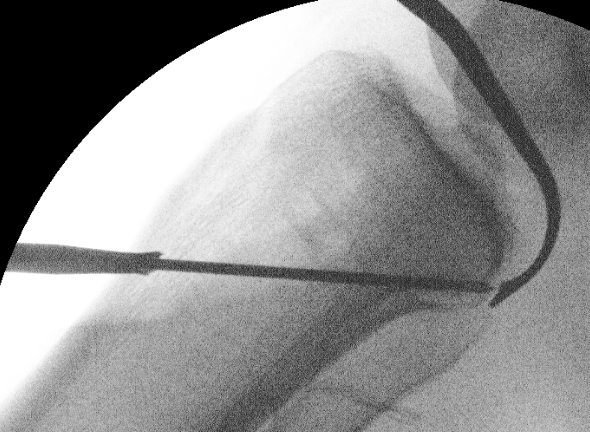

Tibial Tunnel

Incision medial to tibial tuberosity

- PCL jig inserted, usually set at 60 or 65o

- under fluoroscopy, identify the PCL facet

- at least 1 cm below the articular surface

- needs to be more lateral than medial to recreate the anterolateral bundle of PCL

- curette inserted to protect NV bundle

- knee in flexion to protect NV bundle

- beath pin passed

- ream appropriate tunnel (9 or 10 mm for achilles tendon allograft)

PCL tibial tunnelPCL DrillTibial Tunnel PCL

Radiographic location of tibial insertion of PCL

Gali et al, Rev Bras Ortop 2015

- XR assessment AP/lateral

- AP XR: AL and PM bundles 40.68+/-4.10mm and 38.74+/-4.40mm respectively, from the medial edge of tibia

- Lat XR: AL and PM bundles 5.49+/-1.29 and 10.53+/-2.17mm respectively from PCL facet